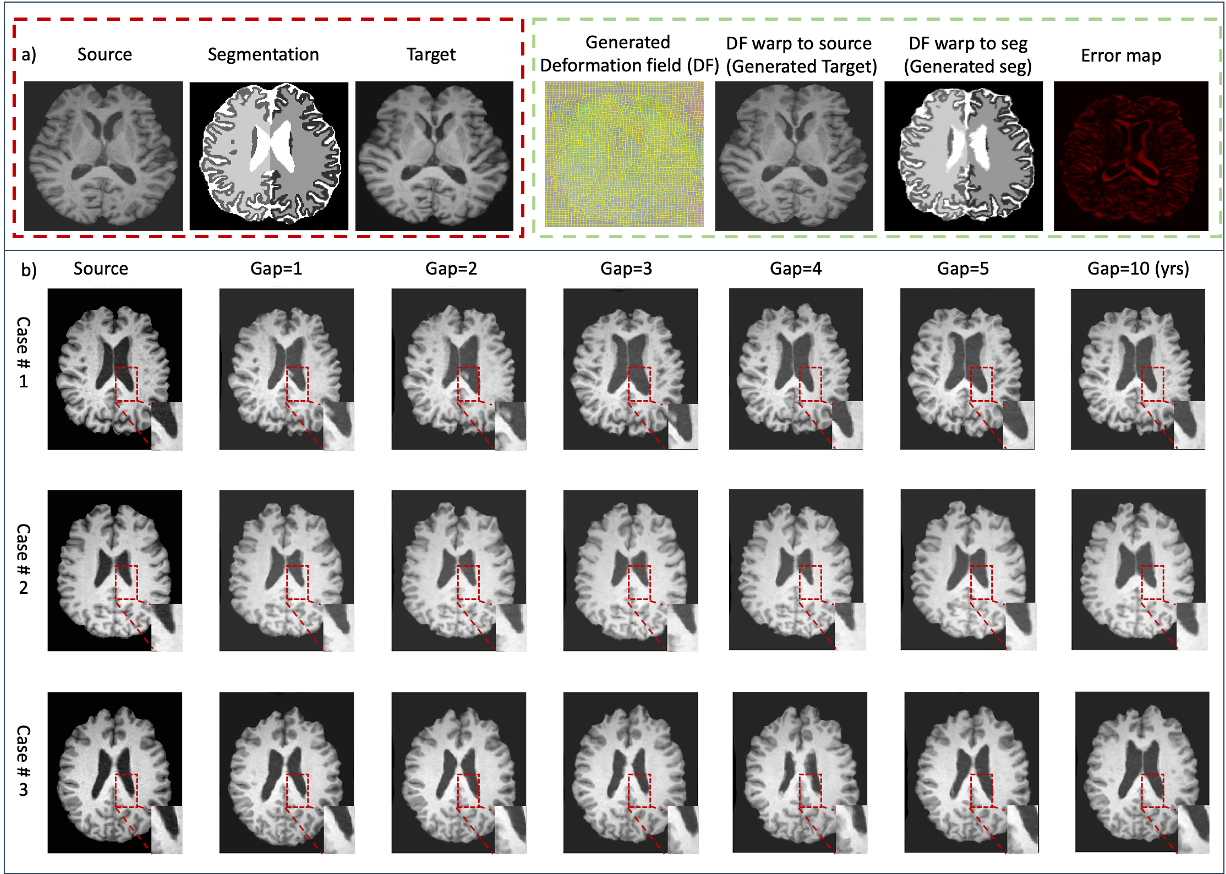

Qualitative Results: As shown in Fig. 2, our method generates realistic aging patterns. For instance, when generating a 70-year-old brain from a 60-year-old source MRI, the model produces plausible ventricular enlargement. The intrinsic modality-agnosticism is demonstrated by applying the same deformation field to both a T1w image and its segmentation map, yielding a consistent pair of future data points. Our model also captures complex, non-linear aging trajectories observed in real data. The apparent ventricular shrinkage in some 2D slices (as seen in some examples) can reflect non-monotonic volume changes over time or be an artifact of slice selection through a 3D structure that is globally, but not uniformly, expanding.

Refer to caption

Figure 2: (a) Our method generates a deformation field (DF) to warp a source image (age 60) and its segmentation map to a target age (70). The generated images show plausible aging effects like ventricular enlargement. (b) Examples of longitudinal generation with increasing age gaps, demonstrating the model’s ability to capture progressive and anatomically consistent changes, such as the gradual expansion of ventricles over time.